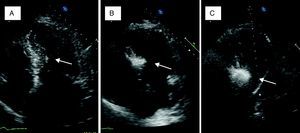

A small amount of angiographic contrast was then injected through the balloon lumen to ensure that there was no spill-back into the LAD or collateral recruitment (Figure 1C). The balloon should not be placed too distally as this may result in a smaller (and solely right-sided) septal infarct, with a consequent reduction in the effect on the outflow gradient. Subsequently, an echocardiographic contrast agent (∼1ml SonoVue, Bracco, Geneva, Switzerland) was injected through the balloon, and the myocardium supplied by the septal artery localized with transthoracic echocardiography (Figure 2). The optimal location within the septum is the point of contact between the anterior mitral valve leaflet and septum in apical four-chamber view. If echocardiographic localization was supportive (no contrast seen outside the thickened basal septum), ablation could proceed. The transvenous pacing wire was re-checked, and intravenous analgesia administered, as the alcohol can cause intense but transient discomfort.

Myocardial contrast echocardiography during alcohol septal ablation. First, the anatomy of the heart is presented and the target septal area is identified (A). Injection of echocardiographic contrast into the target septal branch opacifies the basal part of the septum, verifying the optimal choice of septal branch (B). A more sustained opacification of the basal septum after alcohol injection signifies a good alcohol depot (C).